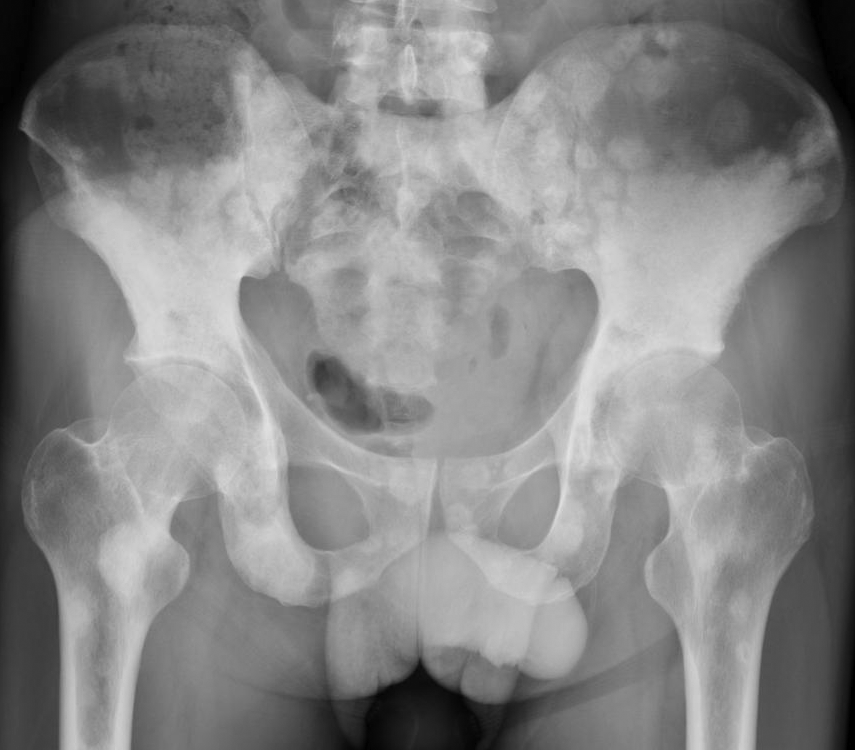

▌地图样破坏

地图样破坏是指肿瘤组织在一个局部呈团块状生长造成界限清楚的骨质破坏(图 1、图 2、图 3、图 4)。病灶可位于骨的中心或一侧部位,呈圆形、卵圆形密度减低区,与正常骨质分界清晰,边缘可有或无硬化带围绕,骨的形态无变化,病灶内可完全透亮或可见粗细不均、大小不等的残留骨嵴,内缘可光滑或呈分叶状压迹。地图样破坏见于大多数良性肿瘤和肿瘤样病变如单纯性骨囊肿、骨纤维结构不良、血管瘤等、也可见于部分恶性骨肿瘤如骨转移瘤、骨髓瘤等。

图 1.地图样破坏:单纯性骨囊肿